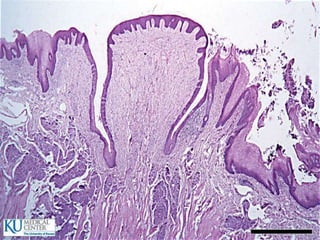

Esófago

 25cm de longitud

 Hacia arriba se continúa con la faringe y hacia abajo

con el estómago

 EPITELIO: Plano estrtificado no queratinizado, en la

parte inferior presenta una transición repentina a

epitelio cilíndrico

 SUBMUCOSA: Fibras colágenas elásticas

 MUSCULAR:

 ADVENTICIA: